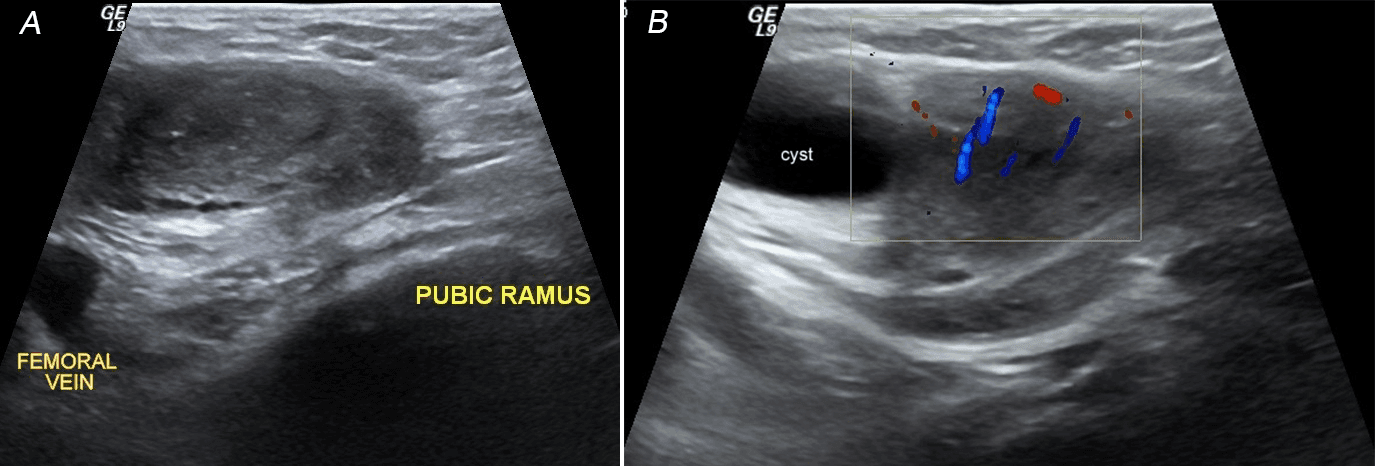

All her laboratory tests were within normal limits. The patient was reviewed by the surgical oncall doctor who made the provisional diagnosis of irreducible right femoral hernia based on the clinical examination. Initially a point of care ultrasound (POCUS) was done by the attending surgical doctor, who was able to appreciate a localized cystic swelling within the hernia sac. A departmental Ultrasonography of the right groin area was obtained to confirm the findings of POCUS. It revealed a well-defined rounded soft tissue echogenicity lesion with a well defined cystic component containing no internal septations or mural nodules. The lesion was located subcutaneously anterior & medial to the femoral vein & reaching medially up to the level of pubic symphysis with no obvious intra-abdominal extension (Figure 1A). The lesion was not reducible and did not change in the size on Valsalva maneuver or cough impulse. No evidence of any peristalsis or free fluid noted within contents of the swelling. Color Doppler imaging revealed central branching pattern of vascularity consistent with ovarian vasculature pattern (Figure 1B). The ultrasound findings were in keeping with right femoral hernia with the ovary within the hernia sac.

Figure 1. Transverse view of the ultrasound scan of the groin swelling revealed ovary lying anterior & medial to the femoral vein.